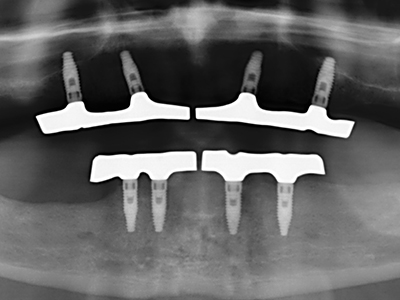

Bei der Knochenblockentnahme zeigen sich weitere Vorteile für die Piezochirurgie: Neben der bereits beschriebenen hohen Präzision bei der Osteotomie stellt sich gerade die Verwendung der dünnen Sägespitzen als besonders materialschonend heraus. Bei der Verwendung insbesondere von Lindemannfräsen sind mit deutlich höheren Entnahmeverlusten durch die dickere Instrumentenspitze zu rechnen (Lakshmiganthan, Gokulanathan et al. 2012). Die insbesondere bei retromolar entnommenen Blocktransplantaten notwendige basale Abtrennung wird durch speziell hierfür vorgesehene rechtwinklige Sägen erleichtert, so dass die Piezochirurgie als präzises, übersichtliches und sicheres Verfahren zur retromolaren Knochenblockgewinnung angesehen wird (Happe 2007) (Abb. 1-12).

Knochengewebe ist nicht nur rein mineralisch, sondern auch in wesentlichen Anteilen aus Kollagenfasern aufgebaut. Dies gewährleistet neben einer guten Druckfestigkeit eine gewisse Flexibilität, welche für die Durchführung von Augmentationen genutzt werden kann. Bei der klassischen Expansionsplastik im Sinne eines Bone Splittings wird der atrophierte Kieferkamm in seiner Längsachse gespalten und nach Erreichen einer ausreichenden Osteotomietiefe vorsichtig aufgedehnt (Abb. 13-16), idealerweise ohne den Kiefer wesentlich zu deperiostieren (Brugnami, Caiazzo et al. 2014, Stricker, Fleiner et al. 2014). Bewährt haben sich Schrauben- und Plattensysteme mit zunehmender Expansionsdistanz, um die beiden Knochenlamellen unterhalb der Bruchschwelle voneinander zu distanzieren. In der Regel werden Restknochenbreiten von mindestens 3-4 mm gefordert (Chiapasco, Zaniboni et al. 2006), um eine ausreichende Flexibilität und knöcherne Bedeckung der einzubringenden Implantate zu gewährleisten. Ggf. kann eine ein- oder beidseitige vertikale Entlastungsosteotomie die Flexibilität verbessern. Als Alternative zur klassischen Technik wurde eine Kombination mit weiteren augmentativen Techniken vor allem auf der bukkalen Seite beschrieben.

Mittels Piezosägen erfolgt die Anlage des Splittings besonders schonend und ohne wesentliche Dimensionsverluste, so dass sich keine signifikanten Unterschiede von Implantaten im gesplitteten Kiefer im Vergleich zum nicht defizitären Alveolarkamm gezeigt haben (Chiapasco, Zaniboni et al. 2006, Danza, Guidi et al. 2009). Gerade beim lokal begrenzten und tiefen Splitting ist jedoch stets auf eine ausreichende Wasserkühlung zu achten, um thermische Belastungen in den apikalen Osteotomiebereichen zu vermeiden.